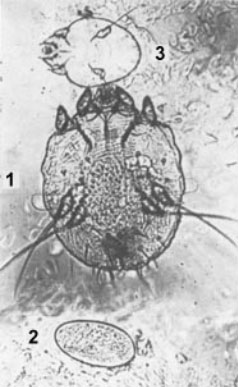

Я посмотрел в микроскоп, где на предметном стекле лежал соскоб, с моей кожи. Там я увидел вот это:

Препарат соскоба чесоточного хода.1. - самка чесоточного клеща с яйцом, готовым к откладке2. - свежеотложенное яйцо3. - подвижные личинки, готовые к выходу из хода

Самка клеща Sarcoptes scabiei имеет овальную черепахообразную форму, размеры 0,3-0,4 мм в длину и 0,25-0,38 мм в ширину, самец в 1,5 раза меньше самки. Ротовые органы клеща несколько выступают кпереди, по бокам находятся 2 пары ножек с присосками и 2 пары задних ножек с щетинками. Яйца зудня овальные, из яиц вылупливаются личинки размером 0,15-0,1 мм, имеющие не 4, как у взрослой особи, а 3 пары ножек.